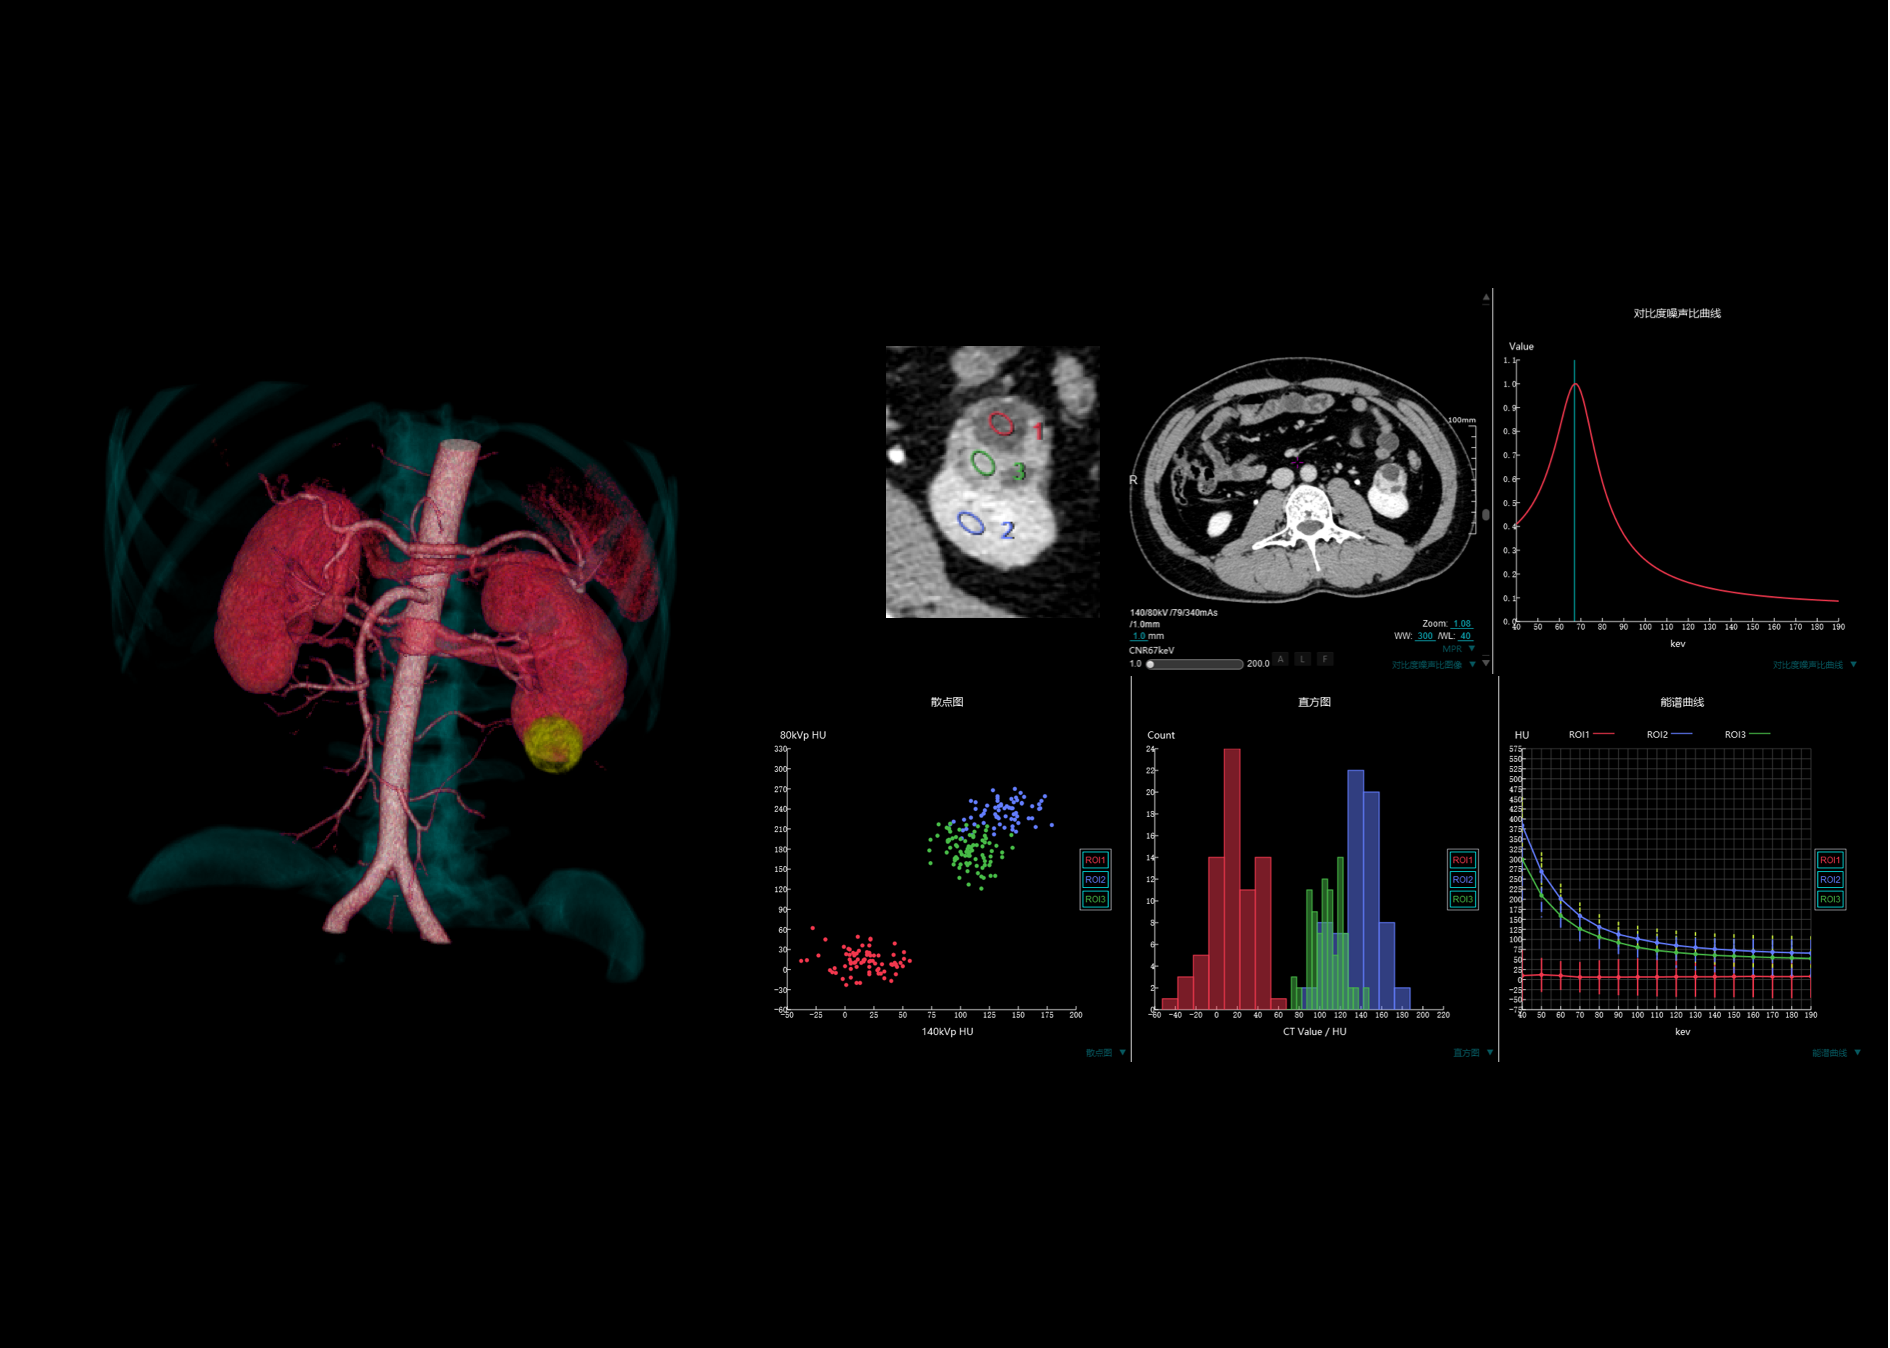

16厘米宽体能谱扫描,不动床轴扫覆盖单器官,获得组织中物质成分和能谱特征的定性及定量分析结果,为临床诊断提供更多可参考信息

用户可根据需求灵活设定准直宽度、采样间隔和剂量,优化患者辐射剂量。同时提供多种灌注协议,自动计算灌注参数

基于动态穿梭扫描技术,天河640可提供最宽40厘米动态成像范围,通过可变床速的扫查和重建,缩短采样间隔